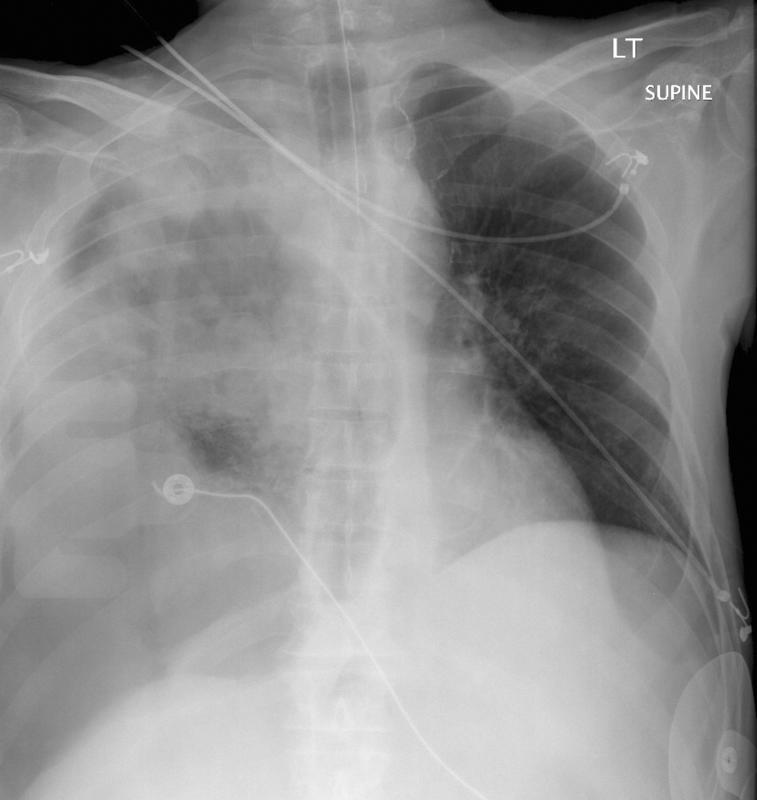

Blunt Chest Trauma

Pneumothorax

8 tension hemopneumo